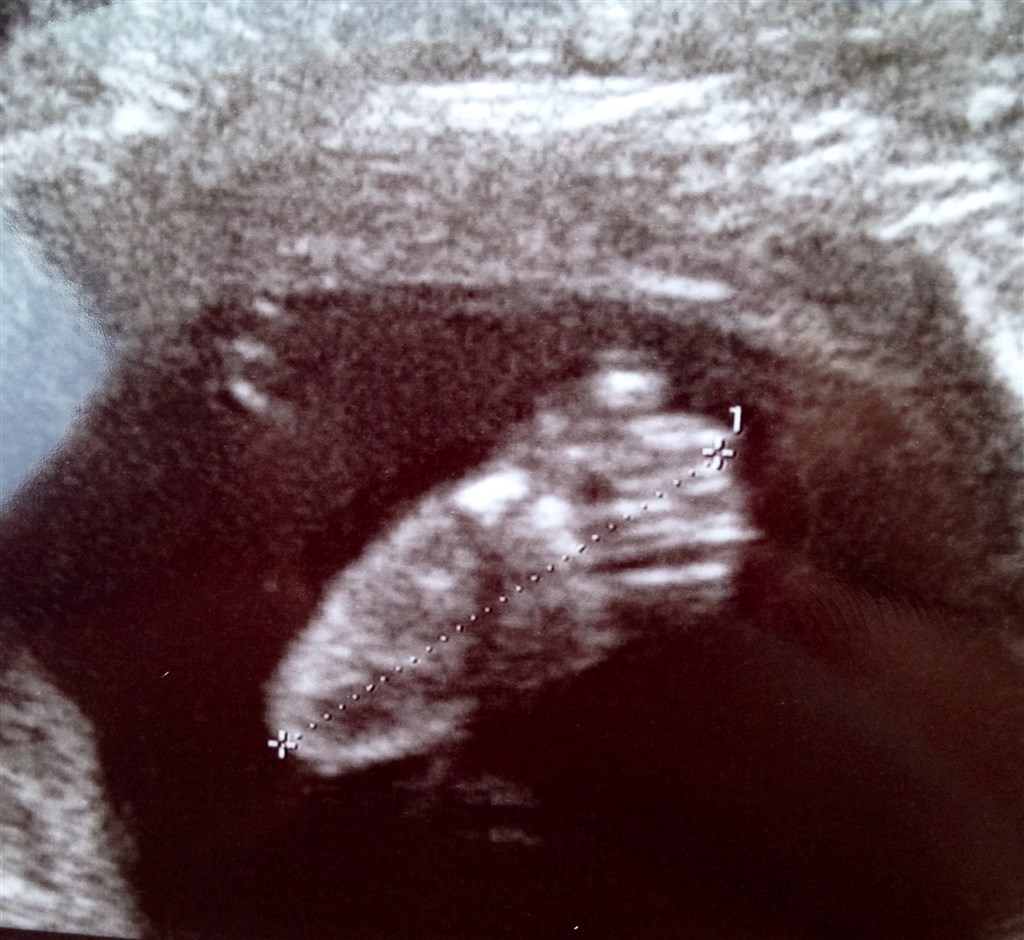

Så har vi i dag været inde og se vores guldklump, og alt så perfekt ud! Det er en rigtig aktiv lille baby der ligger inde i sin hule, og jeg mærker den hver dag!

Det bliver spændende om det er en lille gut eller gutinde der gemmer sig derinde, så nu kan tiden kun gå for langsomt!